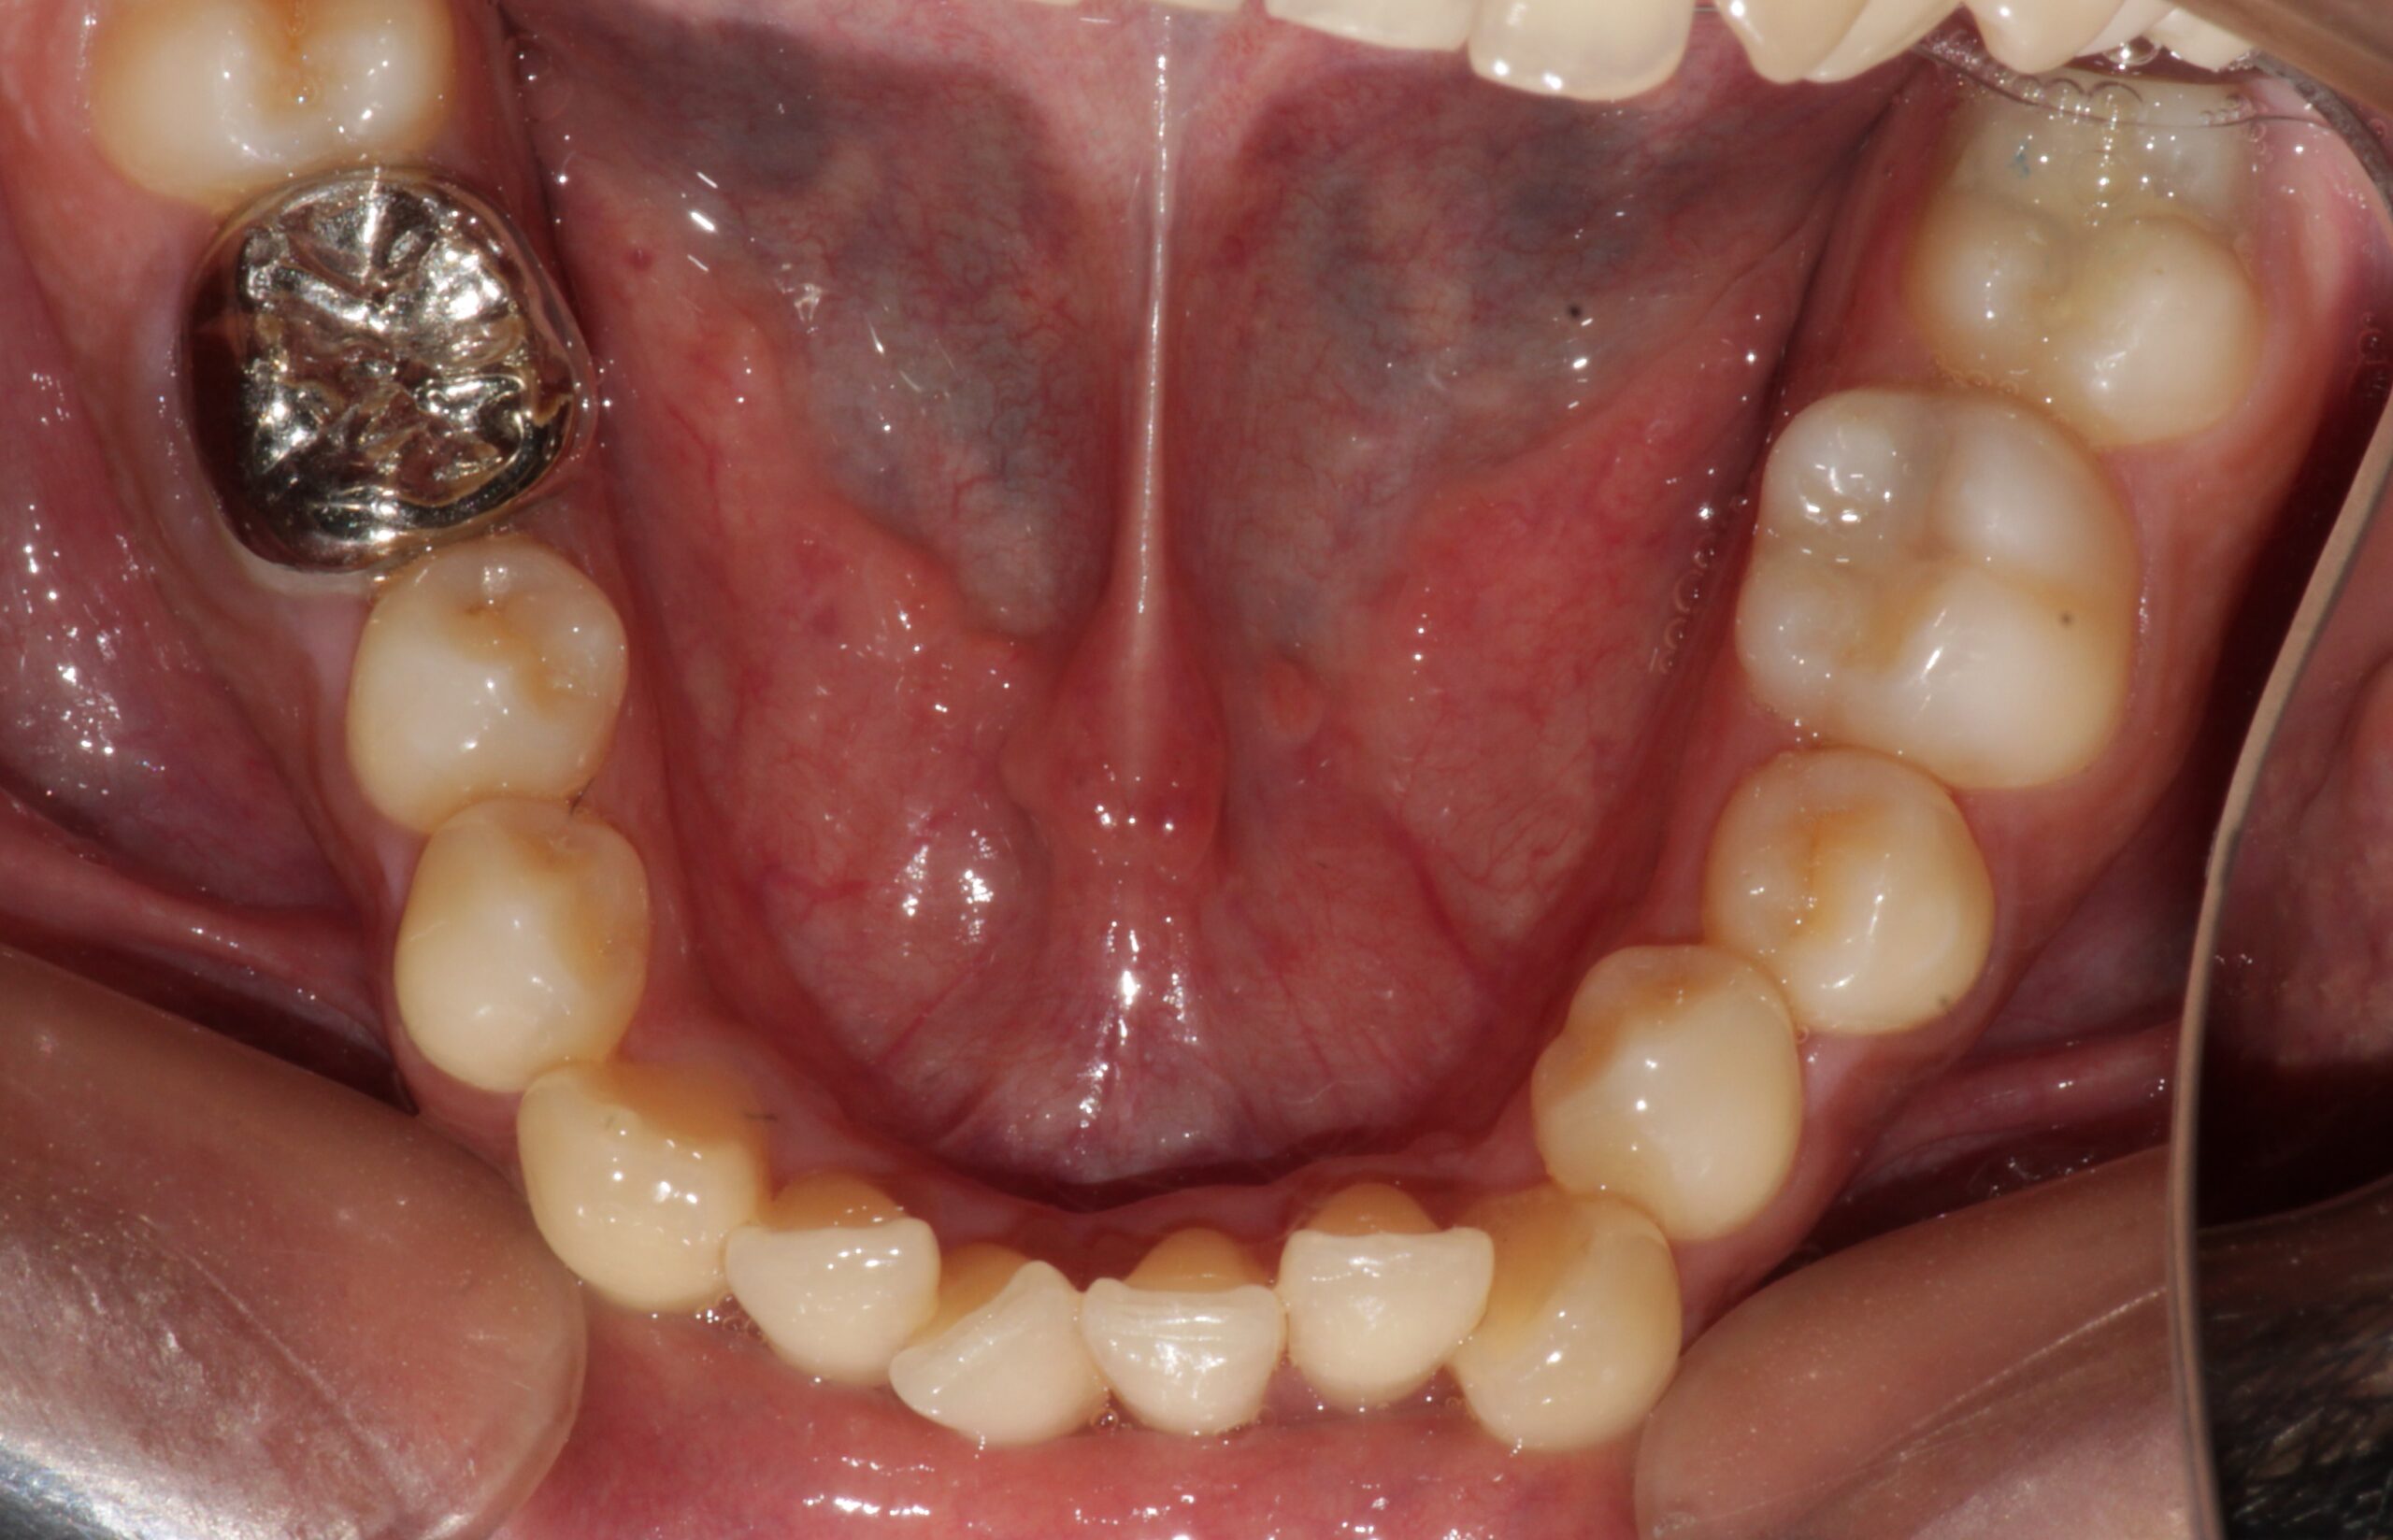

Before: Lower

During The Treatment

After: Lower